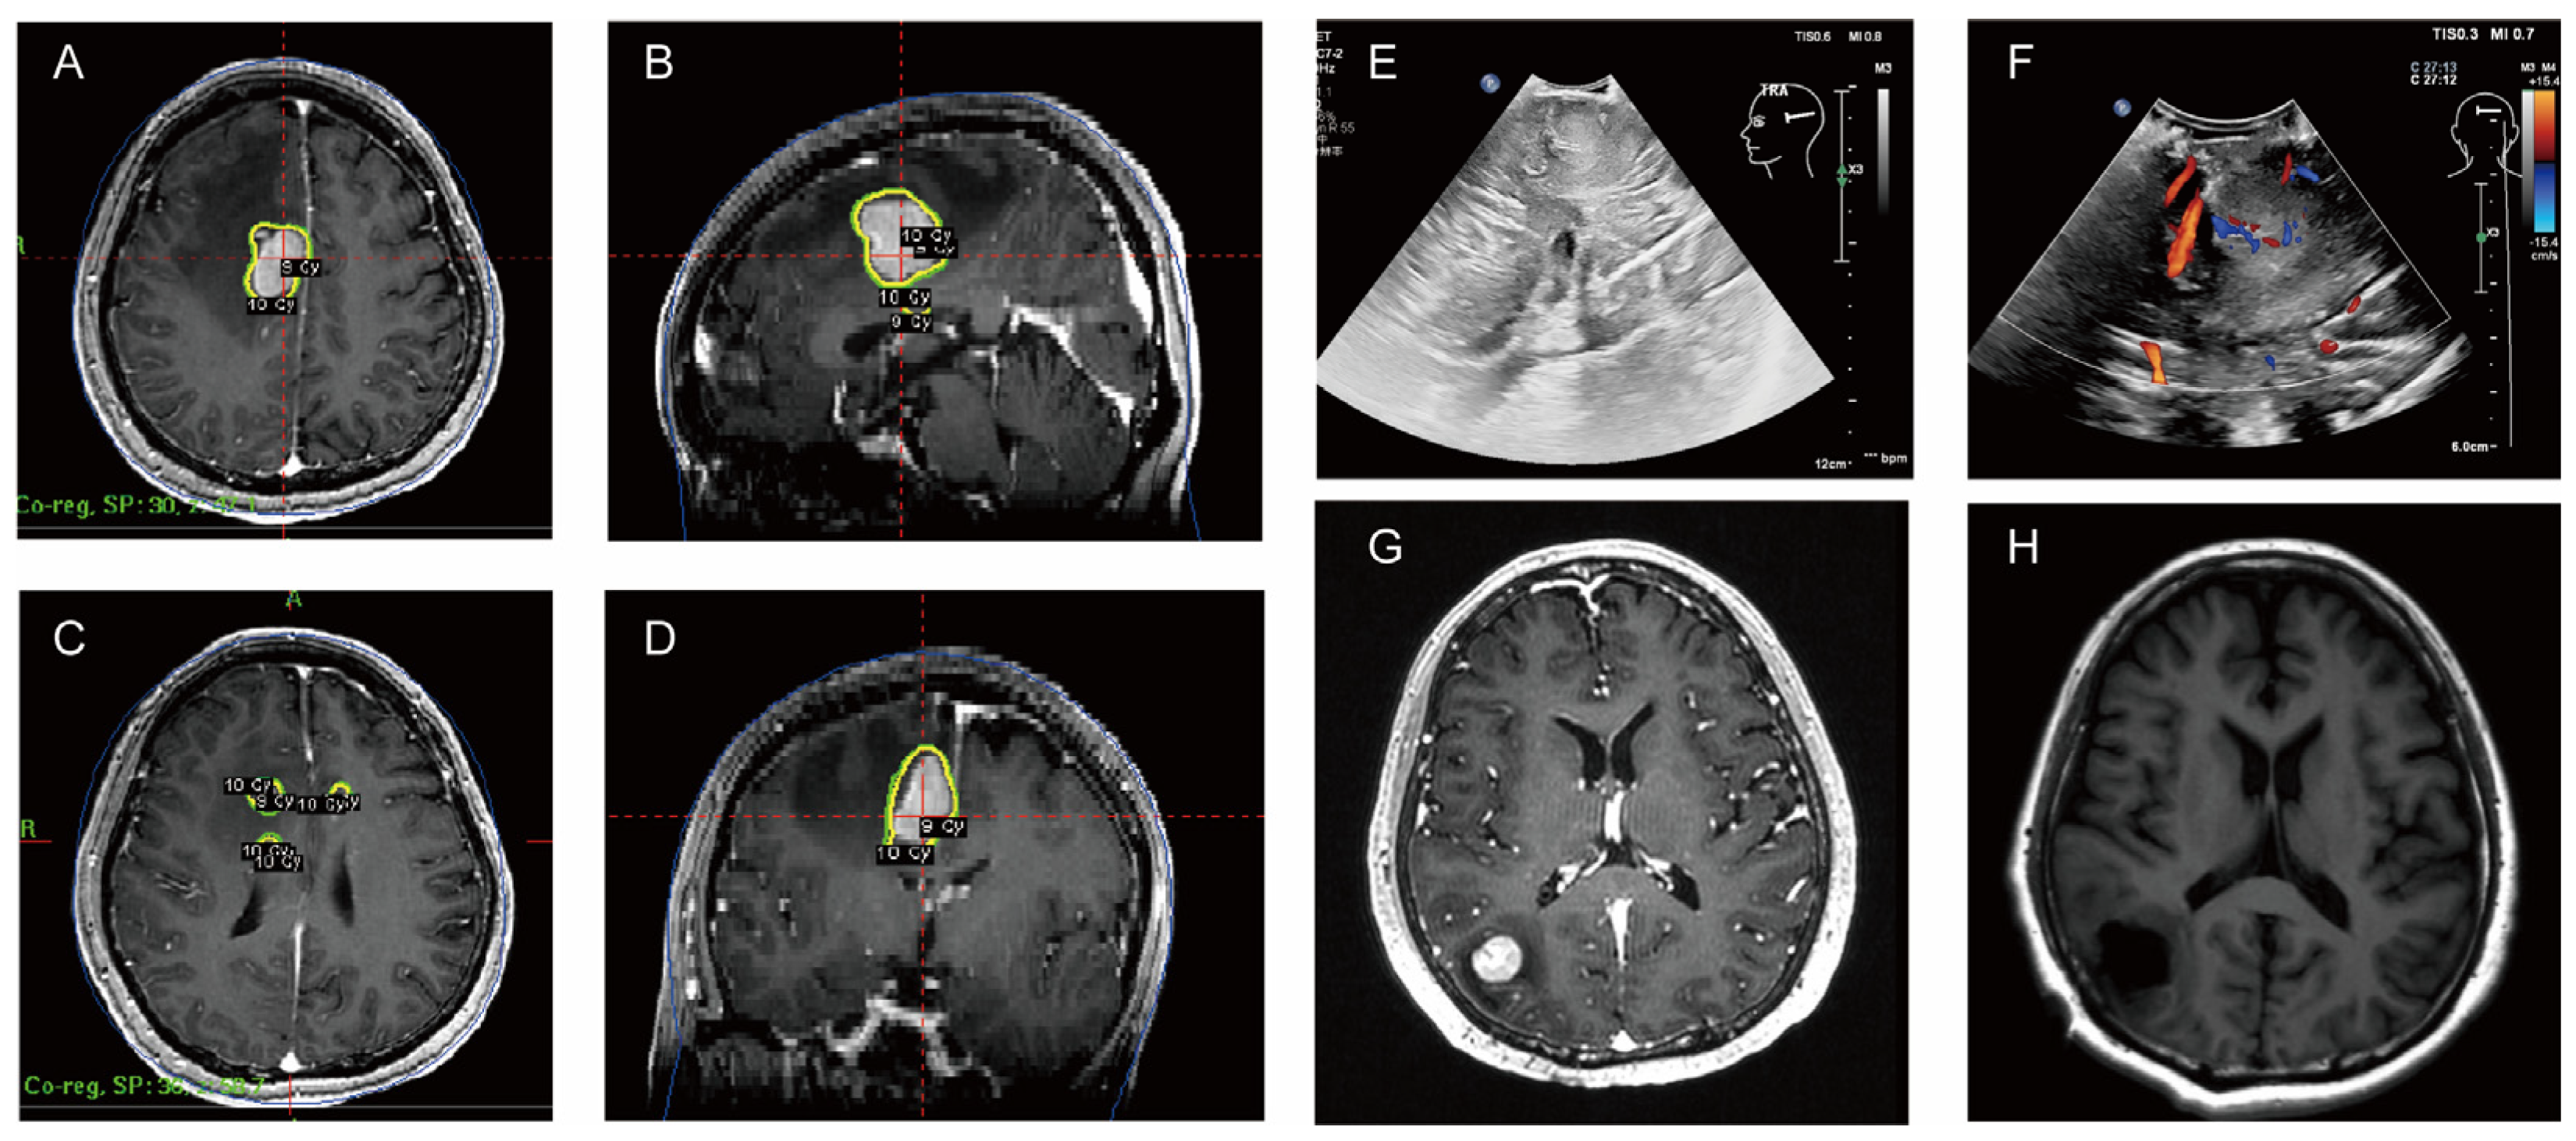

| MRI (4.18): nodular abnormal signals in the right frontal lobe of the brain next to the anterior horn of the lateral ventricle. It was considered to be metastatic tumor accompanied by peripheral odema. | |

| 6 May 2024 | MRI (5.6): multiple intracranial lesions in the right frontal lobe and top of the lateral ventricles. |

| gamma knife radiation therapy | |

| 24 June–9 July 2024 | MRI (6.24): The lesions in the right frontal lobe and the top of the lateral ventricle reduced, but new lesions appeared in the right temporal lobe and occipital lobe. |

| MRI (7.9): Right temporal lobe lesions were smaller, but right occipital lobe lesions were larger. | |

| July 2024 | Surgical resection |

| A C1-POR regimen |